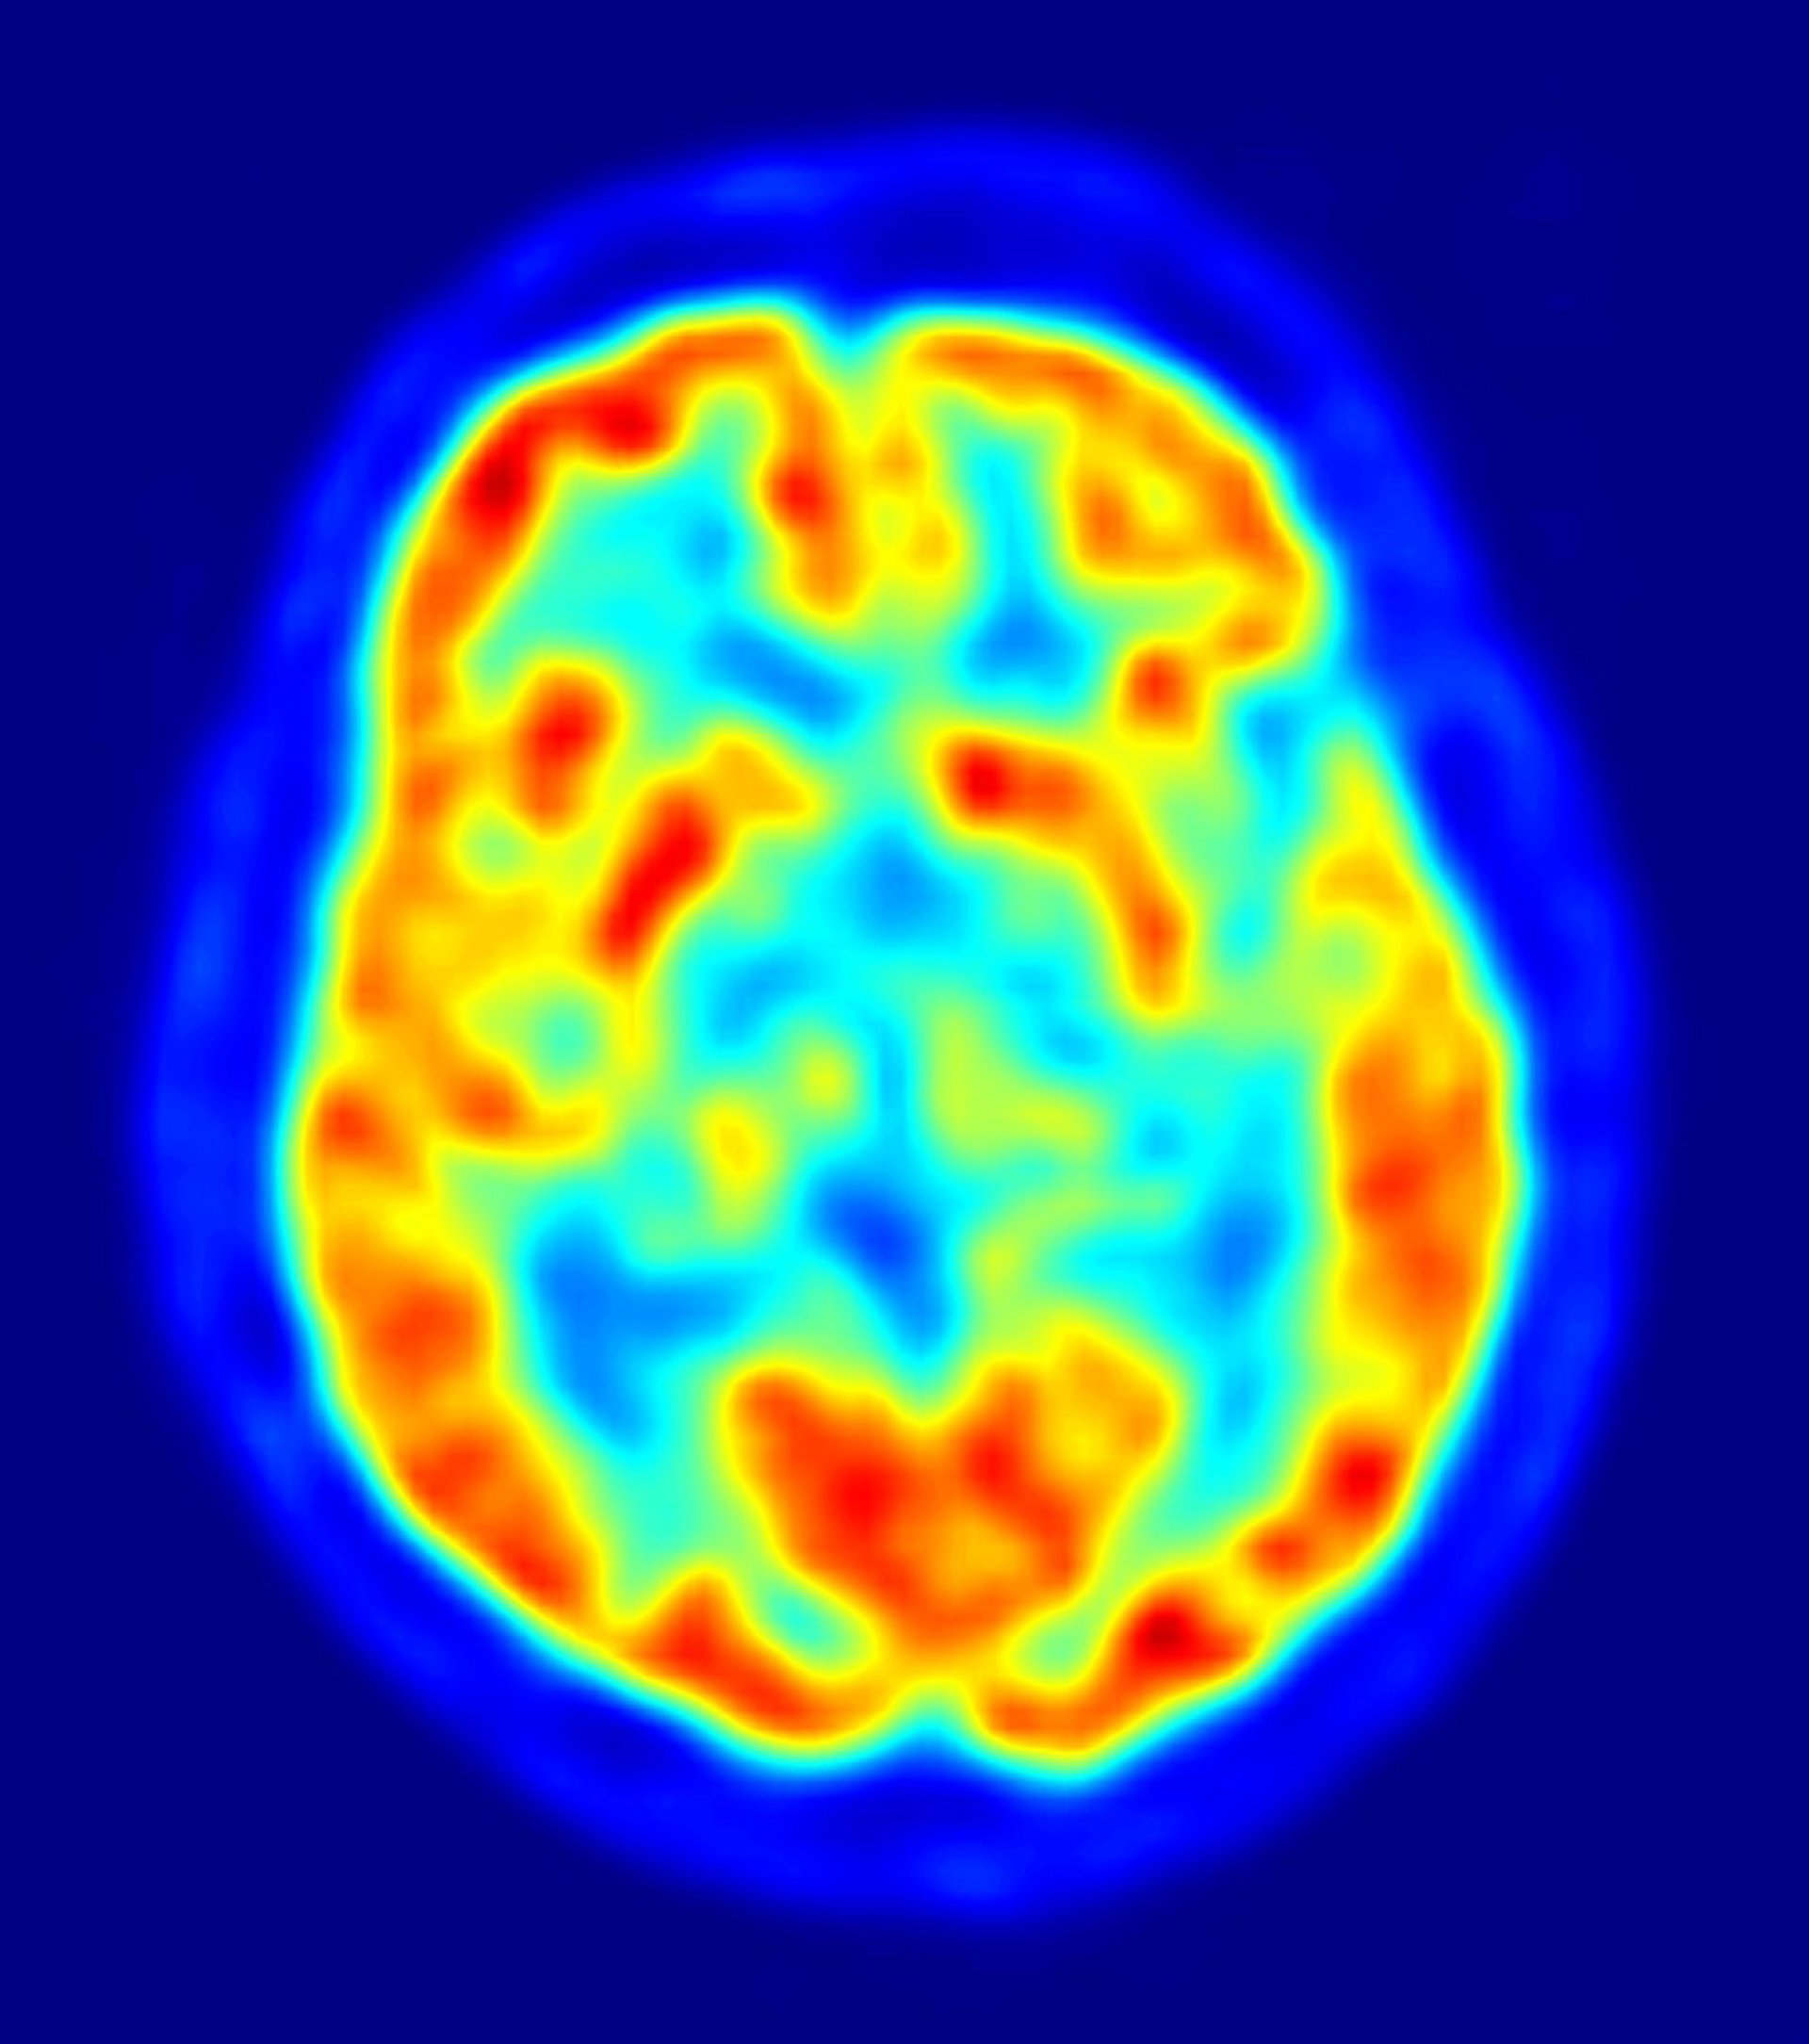

La investigación de las enfermedades complejas humanas como el Alzheimer y otras enfermedades neurodegenerativas relacionadas, no se basa únicamente en la creación de modelos parciales de la enfermedad como los que se desarrollan 'in vitro' o mediante el diseño de animales de experimentación transgénicos.

Por ello, la donación de cerebros es fundamental para poder estudiar las consecuencias de la enfermedad misma sobre el tejido humano, las cuales sirven además como contraste fundamental de los hallazgos experimentales. De hecho, de ellos depende el avance de la investigación.

"Uno de los objetivos primordiales de las investigaciones se centran en reconocer los cambios que se producen progresivamente en el cerebro de los individuos antes de que las enfermedades neurodegenerativas se manifiesten plenamente", por lo que señalan se "hace muy necesario" contar con todo tipo de donantes de cerebro.